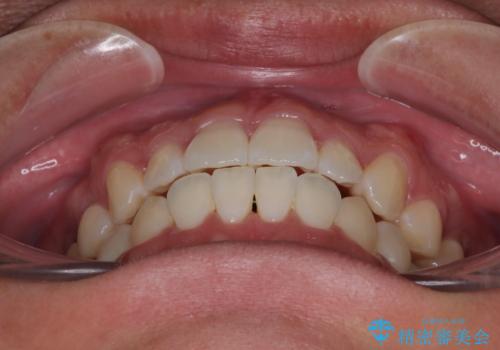

前歯のデコボコをささっと治す 短期間でのインビザライン矯正治療

- 前歯の反対咬合などを気にして来院された患者様です。

ワイヤー矯正、マウスピース矯正どちらでも対応可能であったので、ご本人の希望によりインビザラインにて矯正治療を行うこととしました。

毎日の装着時間をしっかりと守ってくださり、1年強の短期間で、あっという間に治療を終えることができました。